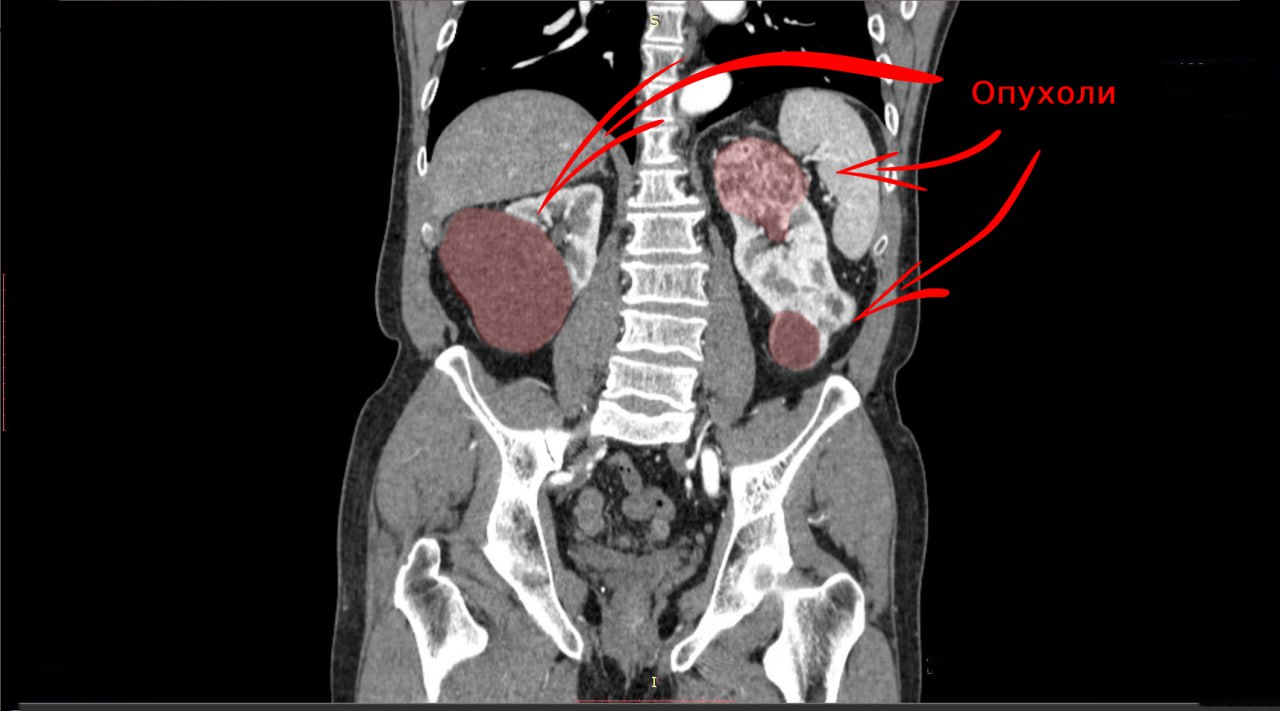

Врачи отделения онкоурологии Свердловского областного онкологического диспансера спасли пациента, у которого обе почки были поражены объёмными злокачественными новообразованиями. Такой синхронный рак встречается редко — лишь в 2-6% случаев. Чтобы сохранить пациенту жизнь и дать ему шанс избежать постоянного гемодиализа, медики успешно выполнили два сложнейших хирургических вмешательства.

Наличие новообразования у свердловчанина заподозрил врач первичного звена системы здравоохранения в ходе планового медосмотра. Мужчину направили для углублённого обследования в Свердловский областной онкодиспансер, где врачи установили, что опухоль в правой почке диаметром более шести сантиметров распространилась почти на 50% паренхимы — важнейшего элемента почечной ткани. Орган удалили, его функции взяла на себя левая почка, но и она была поражена опухолью. Чтобы максимально радикально удалить рак, при этом сохранив жизненно важную функцию почки, онкологи выполнили ещё одну операцию.

«Два новообразования в оставшейся левой почке располагались в верхнем и нижнем сегменте. Это давало возможность сохранить 70% почечной ткани. Удаление опухолей суммарным размером 12 сантиметров выполнили успешно, с минимально короткой ишемией (необходимым снижением притока крови к органу) в 12 минут», — пояснил хирург отделения онкоурологии СООД Александр Орлов.